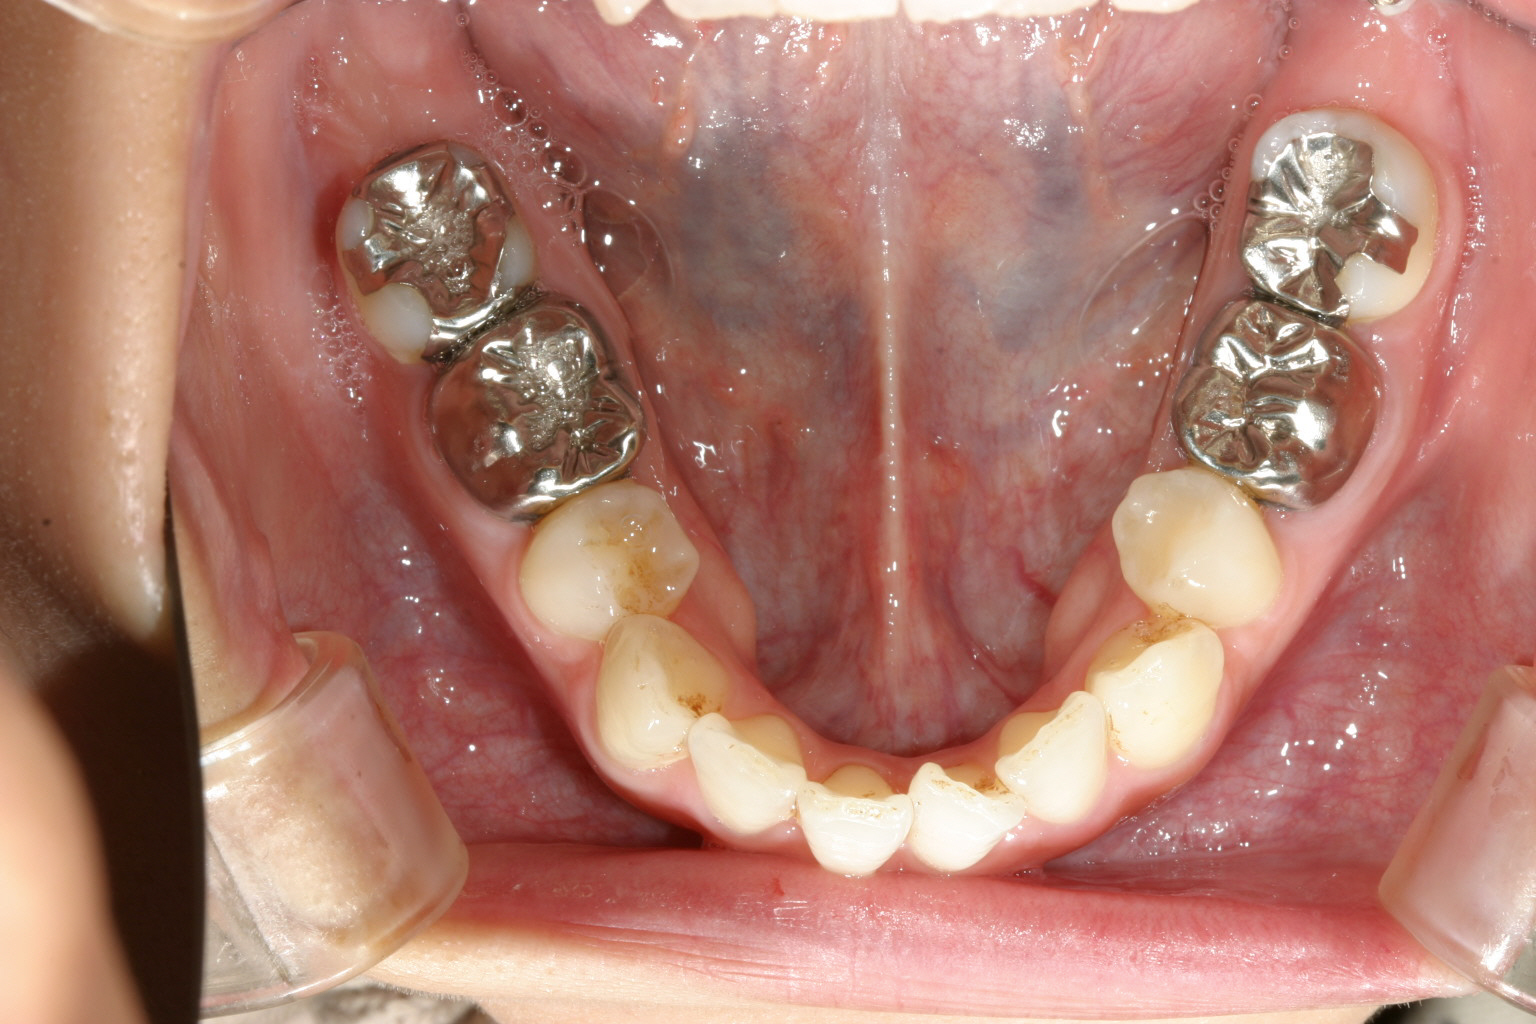

下顎も叢生が出てきています。

下顎も叢生を改善しました。

特に上顎のアーチが狭くなり先が尖って、それに合わせて下顎も叢生が再発していました。